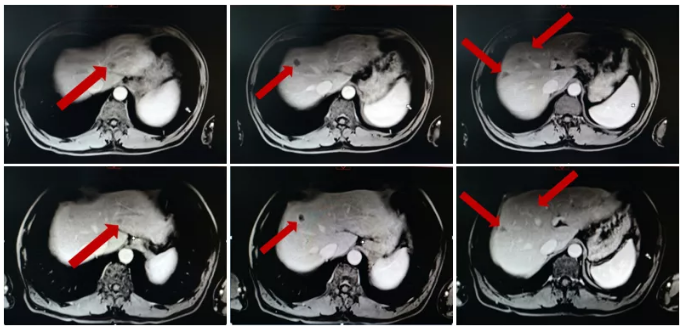

治疗前后病灶变化情况

2018.03-2019.08予以行瑞戈非尼联合Keytruda。

2019.08.18 MRI示腹膜后一增大淋巴结,约2.2cm×1.3cm,DWI弥散受限,环形强化,较前增大,考虑淋巴结转移。

影像学检查

2018.08.19患者现仅腹膜后淋巴结出现进展,其他部位稳定,建议全身治疗不变,行腹膜后淋巴结放疗。

2019.08.26-2019.09.06予以行腹膜后淋巴结姑息放疗45GY/25f。